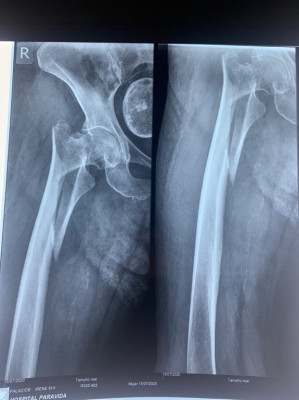

Caso de Fractura de Fémur

Envíado por Dr. Ronald Napoleón Ruano Mendoza